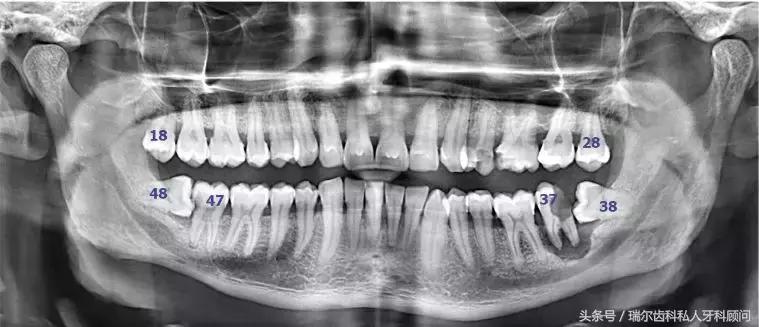

当你觉得自己没有智齿的时候,千万别高兴太早,有可能,你的智齿只是被埋在牙槽骨里了而已,我们肉眼看不到,在他们搞出事情之前,想要发现它们需要拍牙片。而且这种躲在暗处,搞破坏于无形的智齿才最可怕,所以,每年定期做好口腔检查能花小钱办大事,就像体检一样,防患于未然。